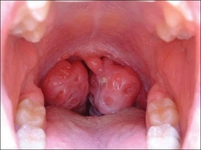

Bademcik İltihabı Nedir?Bademcik iltihabı, bademciklerin (tonsiller) iltihaplanması durumu olarak tanımlanır. Genellikle viral veya bakteriyel enfeksiyonlardan kaynaklanır ve boğazda ağrı, yutkunma güçlüğü ve ateş gibi belirtilerle kendini gösterir. Bademcikler, vücudun bağışıklık sisteminin bir parçası olarak görev yapar ve enfeksiyonlarla savaşmada önemli bir rol oynar. Ancak, aşırı enfeksiyon durumlarında iltihaplanabilirler. Bademcik İltihabının BelirtileriBademcik iltihabı, çeşitli belirtilerle kendini gösterebilir. Bu belirtiler arasında:

Bu belirtiler, bademcik iltihabının ciddiyetine bağlı olarak değişiklik gösterebilir ve bazı durumlarda komplikasyonlara yol açabilir. Bademcik İltihabının NedenleriBademcik iltihabının başlıca nedenleri şunlardır: